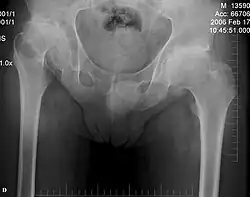

An x-ray showing subluxation at the pelvic bones of the hips.

As individuals with DMC syndrome age, skeletal changes can cause challenges, potentially requiring surgery to improve quality of life.[2][7] These secondary symptoms include spinal compression, dislocated hips, reduced mobility/range of motion, scoliosis, lumbar lordosis, thoracic kyphosis, and subluxation.[2][3][7] Secondary symptoms can appear as early as adolescence and will persist throughout an individual's life.[3]

For hip dysplasia, which is currently believed to be epiphyseal in origin, various treatment options and surgical procedures have been explored, including realignment of the proximal femur and/or acetabulum, realignment osteotomy, cheilectomy, and in more advanced cases, total hip replacement (THA).[2][7] However, studies suggest that osteotomies, including femoral and pelvic osteotomies, often fail to prevent the progression of hip subluxation and femoral head migration and may lead to progressive degeneration of the hip joint.[1][7][8]

Regardless of the method used to treat hip dislocation and avoid further joint damage, it appears to progress into complete hip degeneration over time.[7]